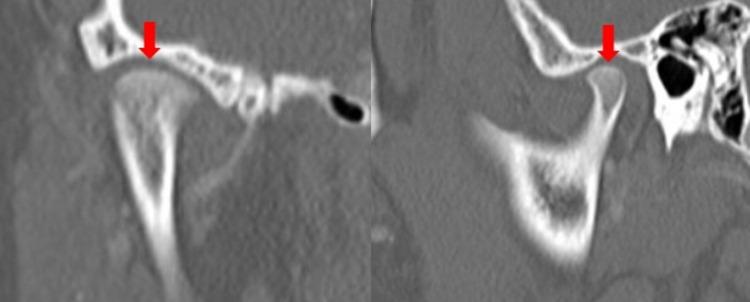

Bifid mandibular condyle (BMC) is splitting the mandibular condyle into two separate articular surfaces. The etiology is poorly understood, but trauma and developmental issues are currently the most cited causes. Though most often asymptomatic, occasionally, this condition may cause the development of jaw pain, clicking, and restriction of motion. We present a rare case of a patient who developed unilateral ankylosis of the temporomandibular joint (TMJ) secondary to BMC in the absence of trauma or infection. The ankylosis developed due to abnormal biomechanical forces and degenerative arthritis secondary to the abnormal articulation of the TMJ caused due to BMC. CT imaging is the best modality to evaluate the bony anatomy of the TMJ. It is essential to consider BMC as a cause of TMJ pathology, as management is primarily surgical in nature.

双侧下颌髁突(BMC)是指下颌髁突分裂为两个独立的关节面。其病因尚不清楚,但目前最常提及的原因是创伤和发育问题。尽管大多数情况下无症状,但偶尔这种情况可能会导致颌部疼痛、弹响和运动受限。我们报告了一例罕见病例,一名患者在没有创伤或感染的情况下,继发于BMC出现了颞下颌关节(TMJ)单侧强直。强直是由于BMC导致TMJ异常关节连接所产生的异常生物力学力量和退行性关节炎引起的。CT成像 是评估TMJ骨解剖结构的最佳方式。必须将BMC视为TMJ病理的一个原因,因为治疗主要是手术性质的。